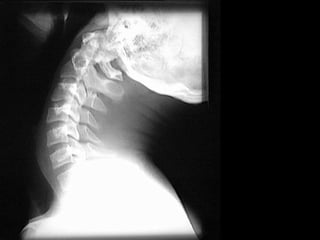

CERVICAL EM PERFIL Posição do Paciente:  Ortostática, com os braços para traz e com as mãos dadas forçando os ombros para baixo; Alinhando a linha médio coronal com a linha média da estativa, estenda levemente o queixo para a frente (a fim de evitar a sobreposição da região cervical superior pela mandíbula); Raio Central:  Perpendicular horizontal, incidindo ao nível de C4; Filme:  18x24 em longitudinal, borda superior do chassi 3cm acima do meato acústico externo; DFF:  de 150 cm.

CERVICAL EM PERFIL

ESTRUTURAS DEMOSTRADAS

CERVICAL EM PERFIL Posição do Paciente:  Ortostática, com os braços para traz e com as mãos dadas forçando os ombros para baixo; Alinhar a linha médio coronal com a LCE, estenda levemente o queixo para a frente (a fim de evitar a sobreposição da região cervical superior pela mandíbula); Raio Central:  Perpendicular horizontal, incidindo ao nível de C4; Filme:  18x24 em longitudinal, borda superior do chassi 3cm acima do meato acústico externo; DFF:  de 150 cm.